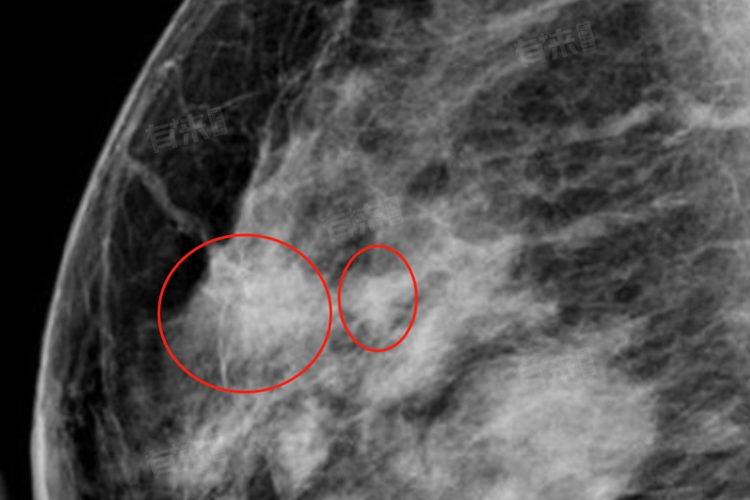

- 乳腺结节:可能与遗传、环境因素、内分泌激素水平、基因突变等相关。恶性乳腺结节可能表现为乳腺形态不规则,与周围组织分界不清,结节周围可出现模糊、分叶、毛刺状改变。